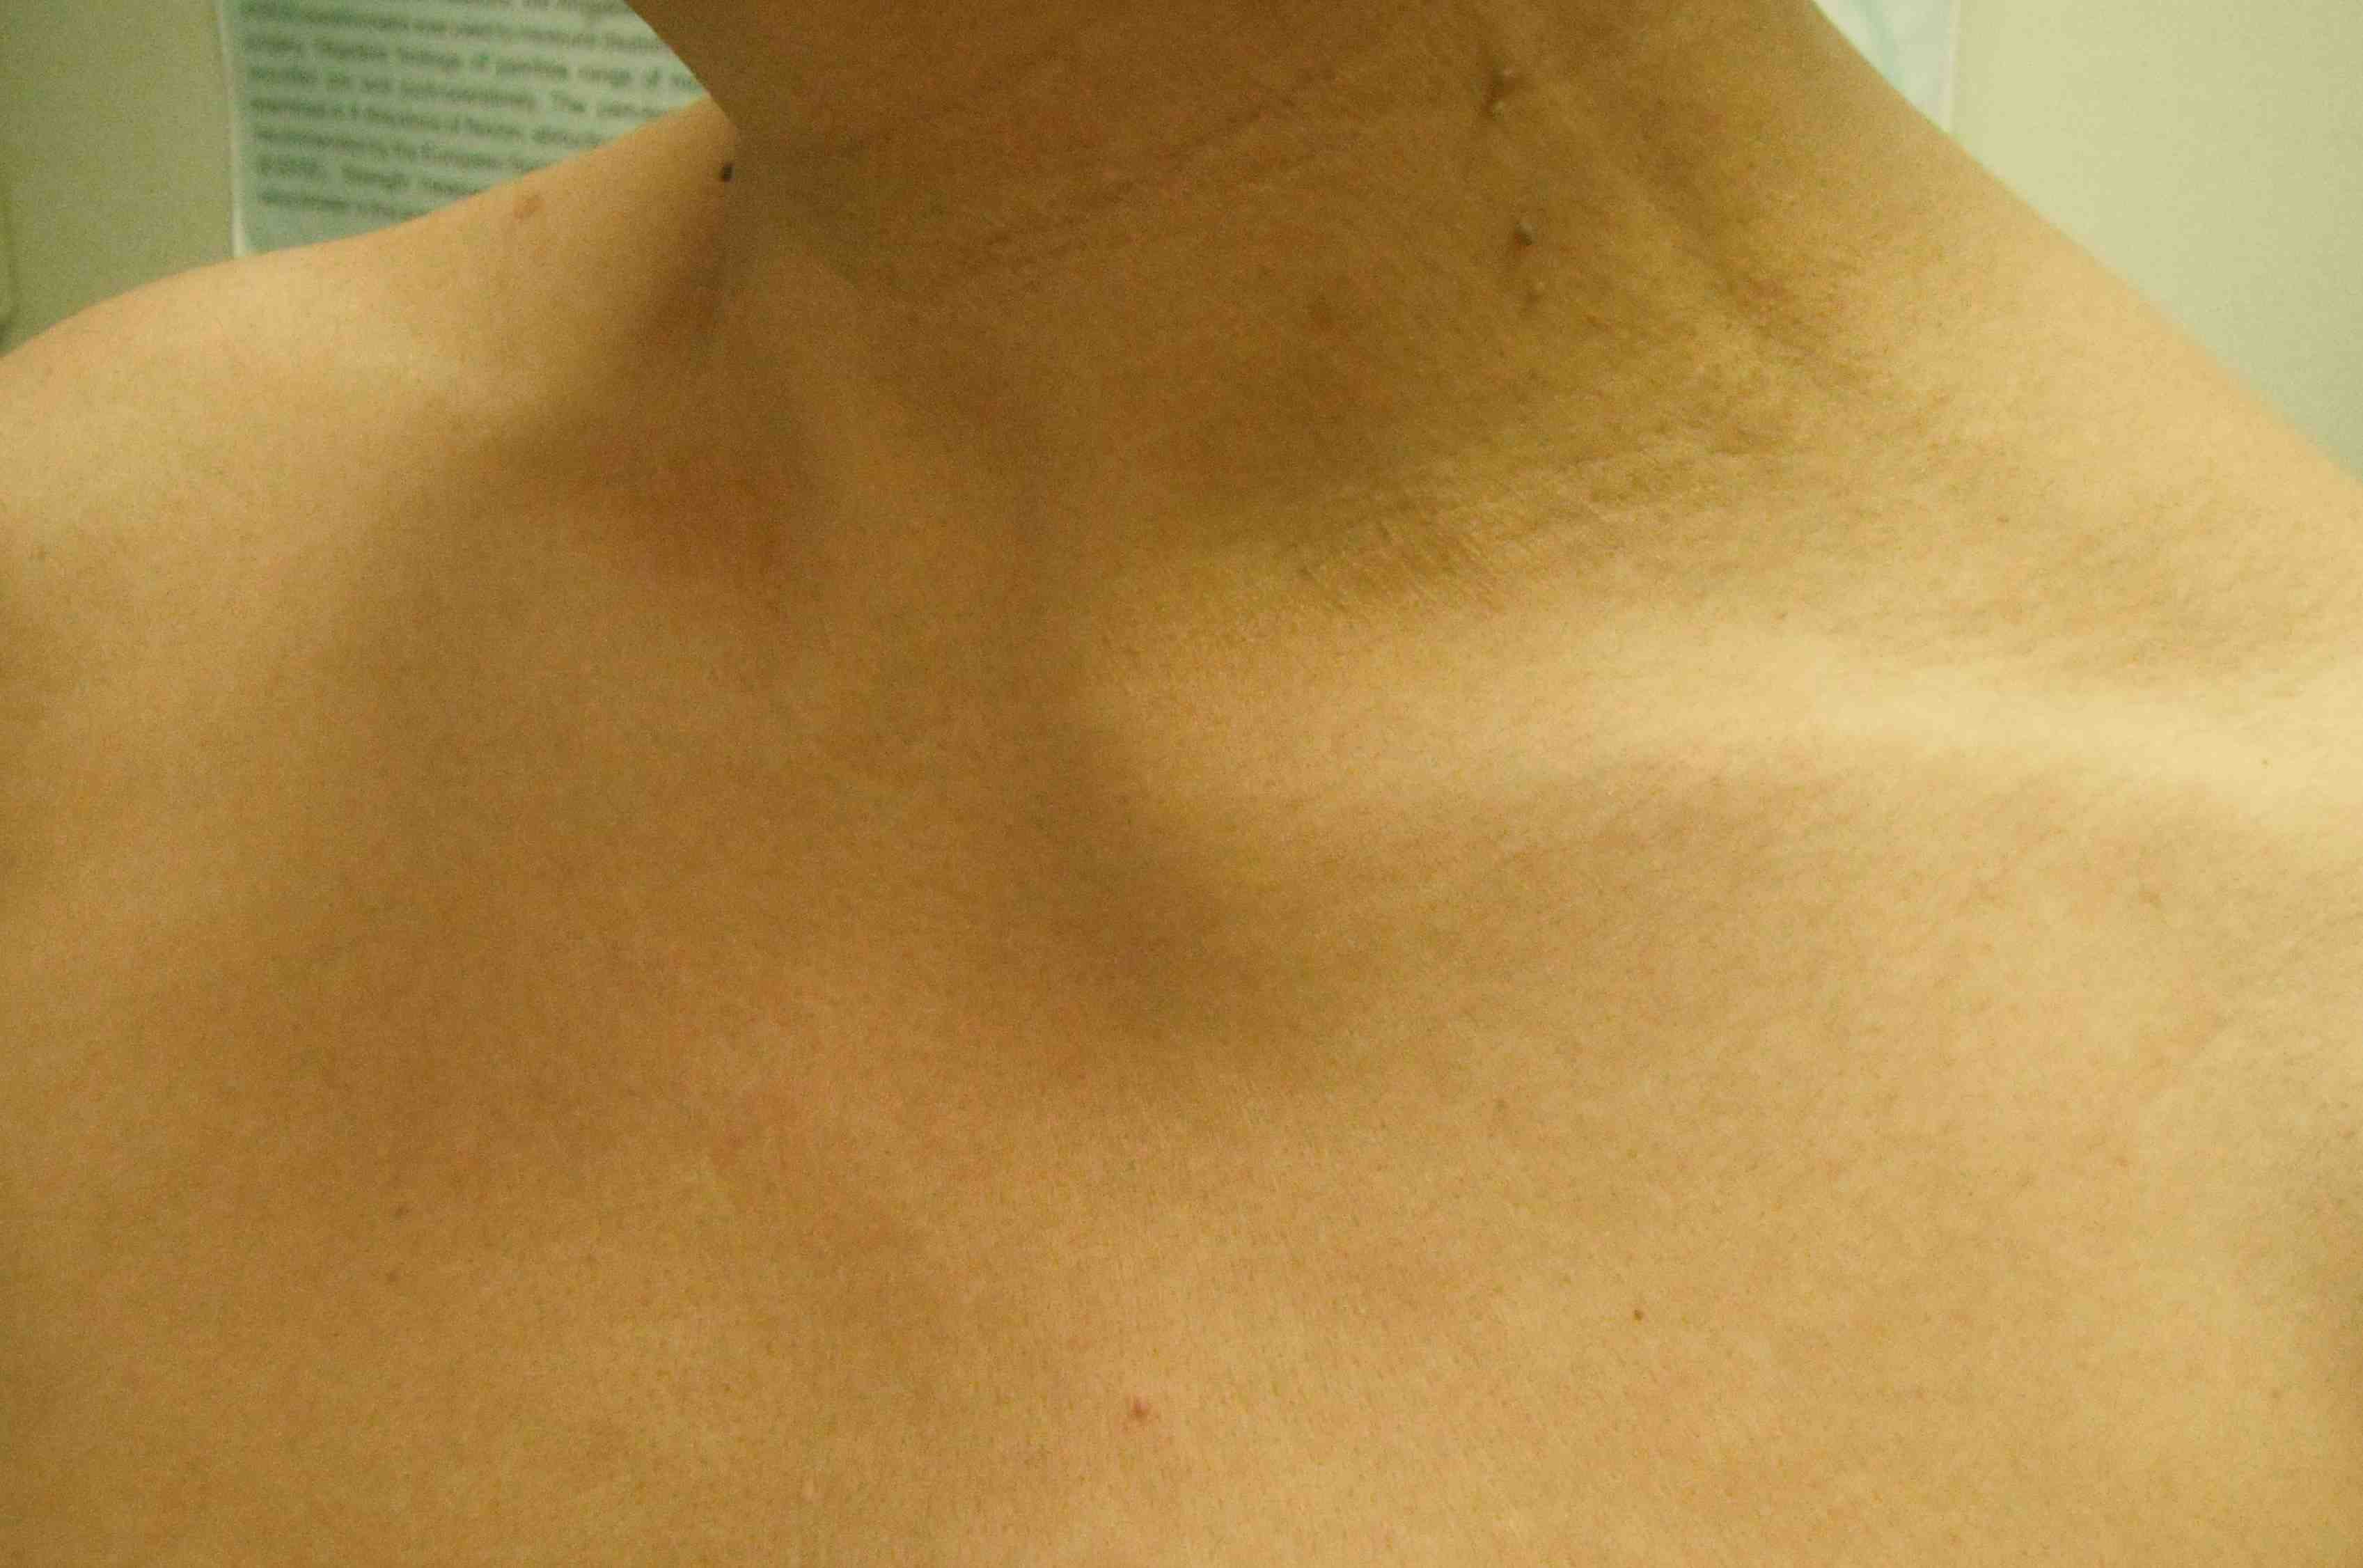

Clinical presentation

Can impinge on airway and posterior neurovascular structures

- shortness of breath

- difficulty swallowing / dysphagia

- neurological or vascular compromise -

Presentation

Medial pain and swelling over 1 - 2 weeks